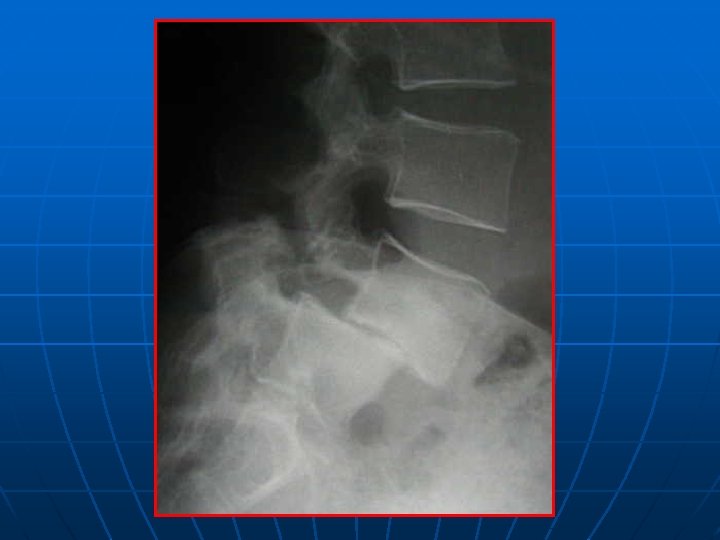

BILAN RADIOLOGIQUE STANDARD +++ n n SIGNES INDIRECTS DE CLE: *sagittalisation de l’IA *hypertrophie des articulaires *pédicules courts Spondylolesthésis dégénératif sagittal et frontal Visée pédiculaire: taille du pédicule+point d’entée CLICHES DYNAMIQUES INDISPENSABLES : Instabilité surtout en flexion

SPONDYLOLESTHESIS ISTHMIQUE Rx standard: face+profil+3/4 D-G Découverte au stade de déplacement n Lombalgies isolées: pas d’autres explorations n Lombosciatiques: Rx dynamiques+ grand format+IRM ( TDM peu d’apport) n